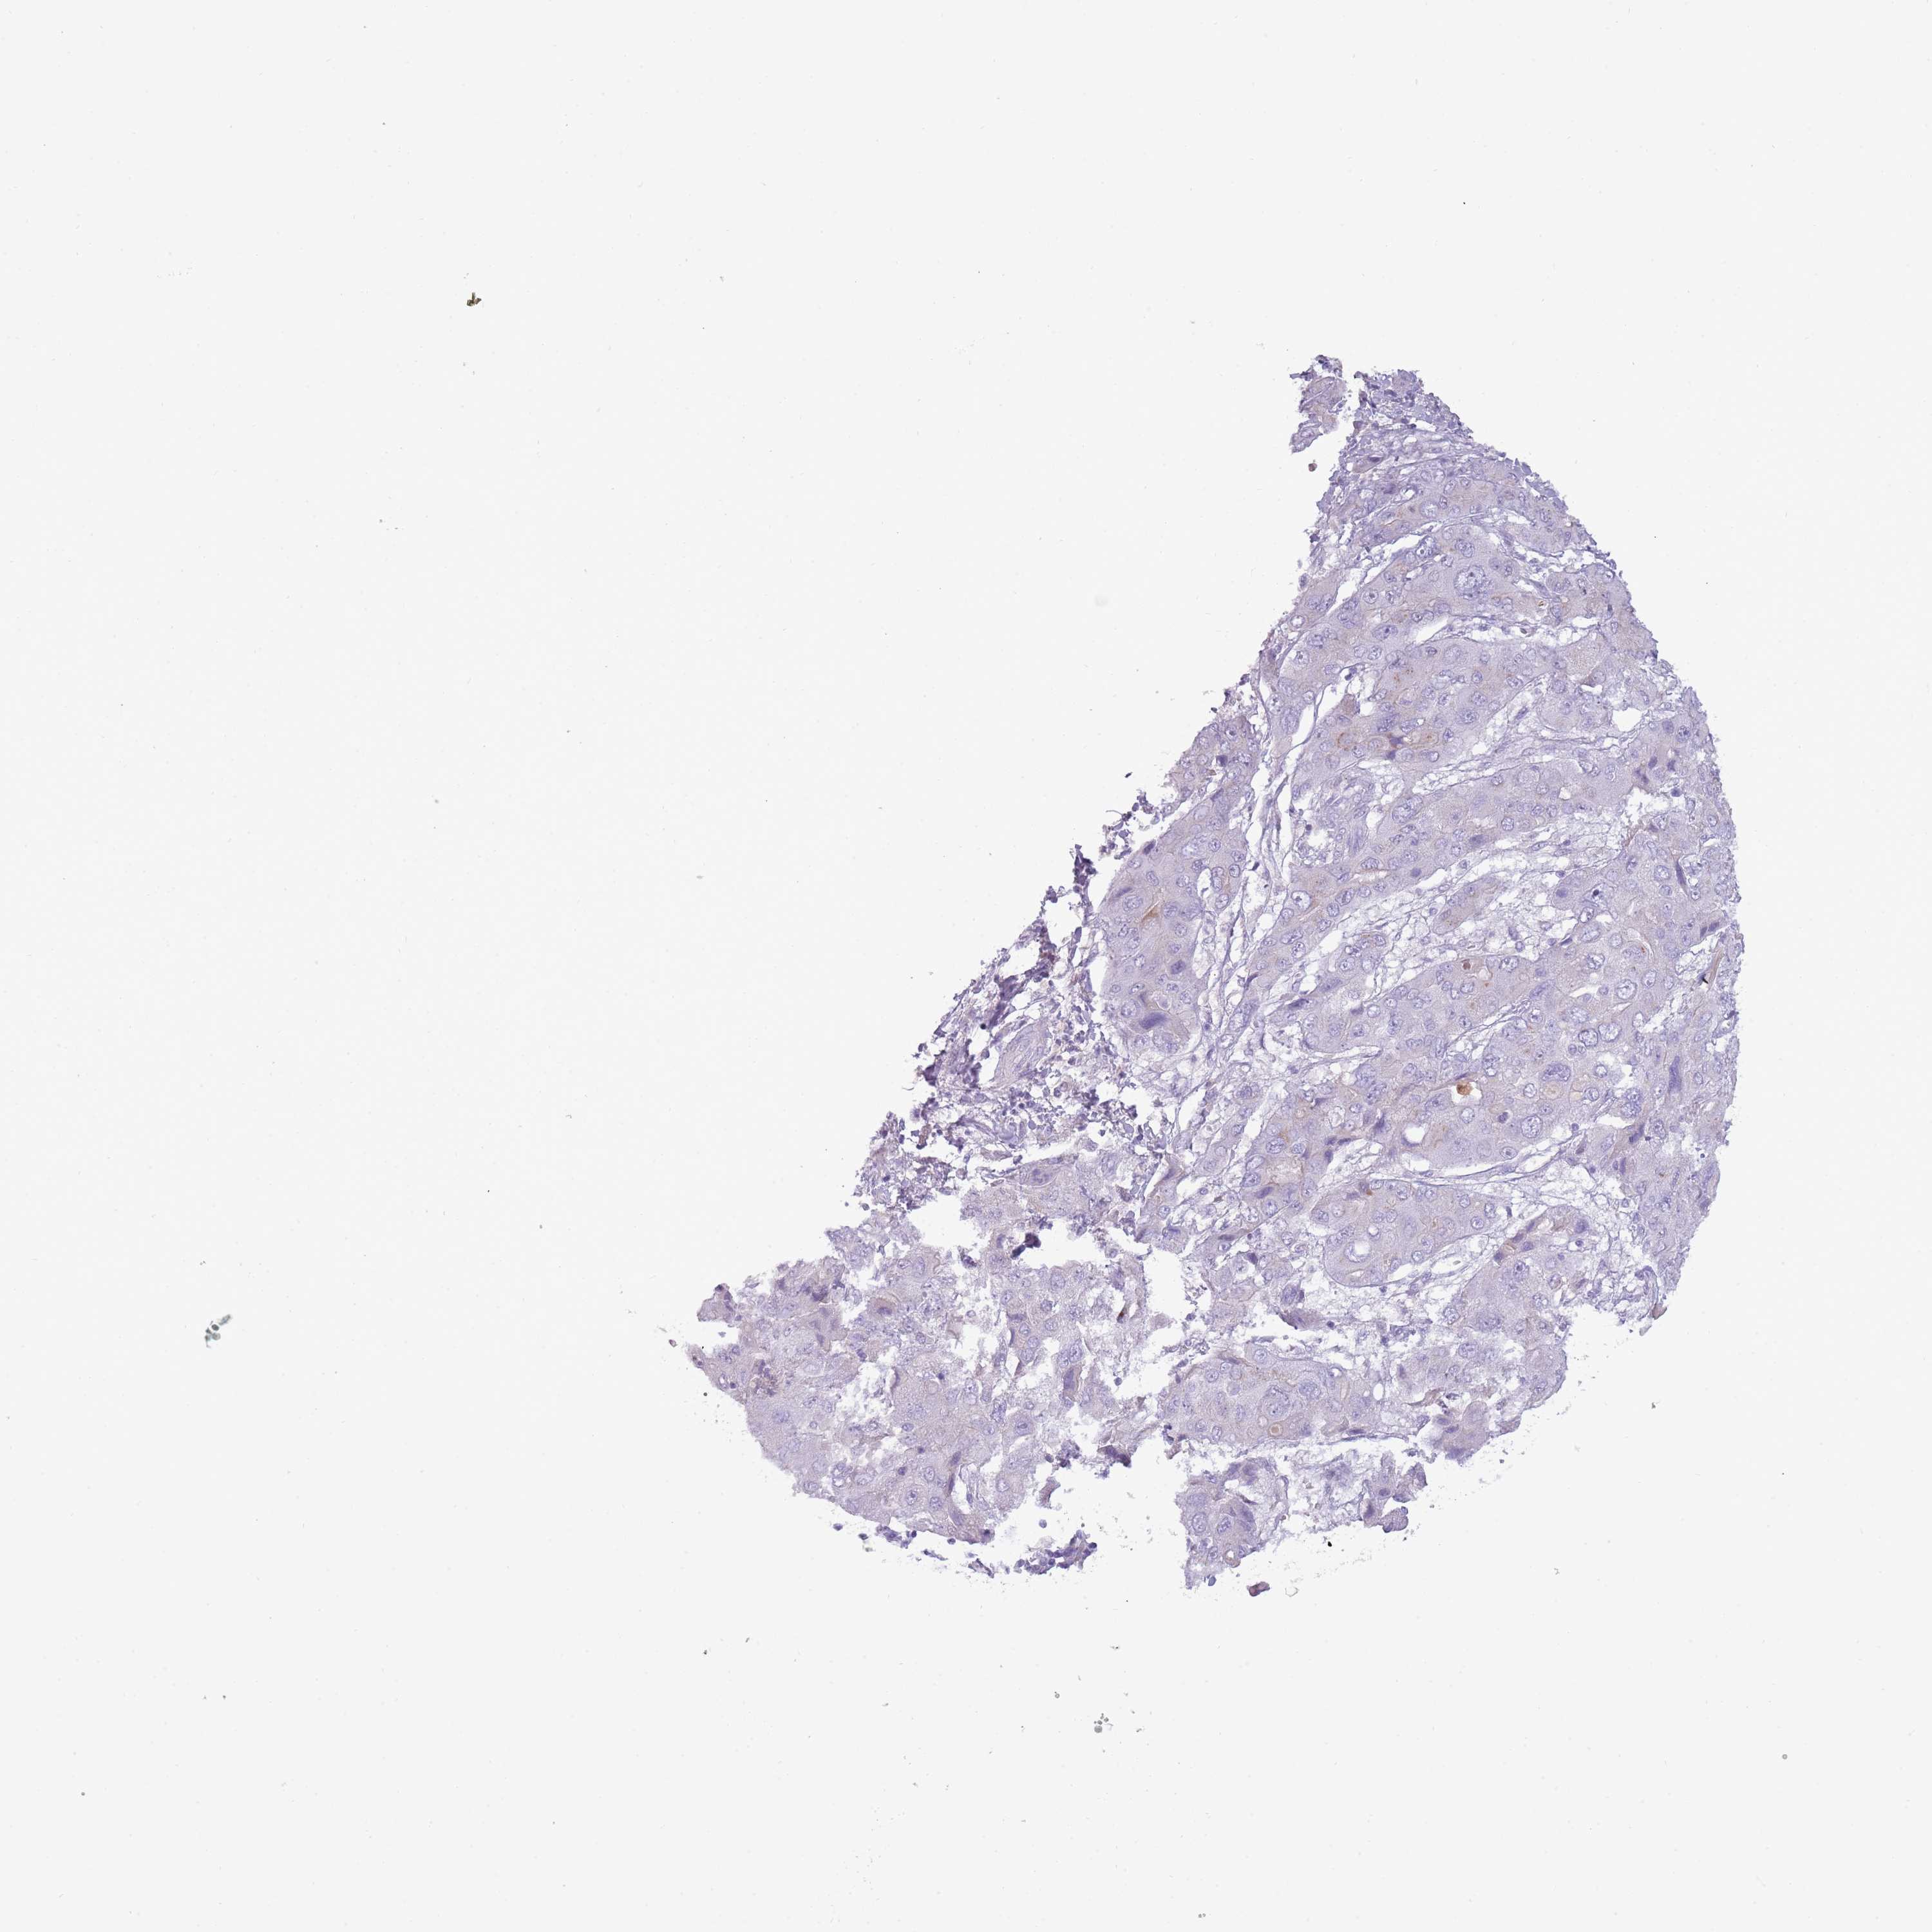

LIVER CANCER - Protein expressioni

A mouse-over function shows sample information and annotation data. Click on an image to view it in a full screen mode. Samples can be filtered based on level of antibody staining by selecting one or several of the following categories: high, medium, low and not detected. The assay and annotation is described here.

Note that samples used for immunohistochemistry by the Human Protein Atlas do not correspond to samples in the TCGA dataset.

Antibody stainingi

Antibody staining in the annotated cell types in the current human tissue is reported as not detected, low, medium, or high, based on conventional immunohistochemistry profiling in selected tissues. This score is based on the combination of the staining intensity and fraction of stained cells.

Each image is clickable and will lead to virtual microscopy that enables deeper exploration of all samples and also displays staining intensity scores, fraction scores and subcellular localization as well as patient and tissue information for each sample.

Antibody HPA045044

Antibody HPA046411

Antibody HPA047447

Antibody HPA058050